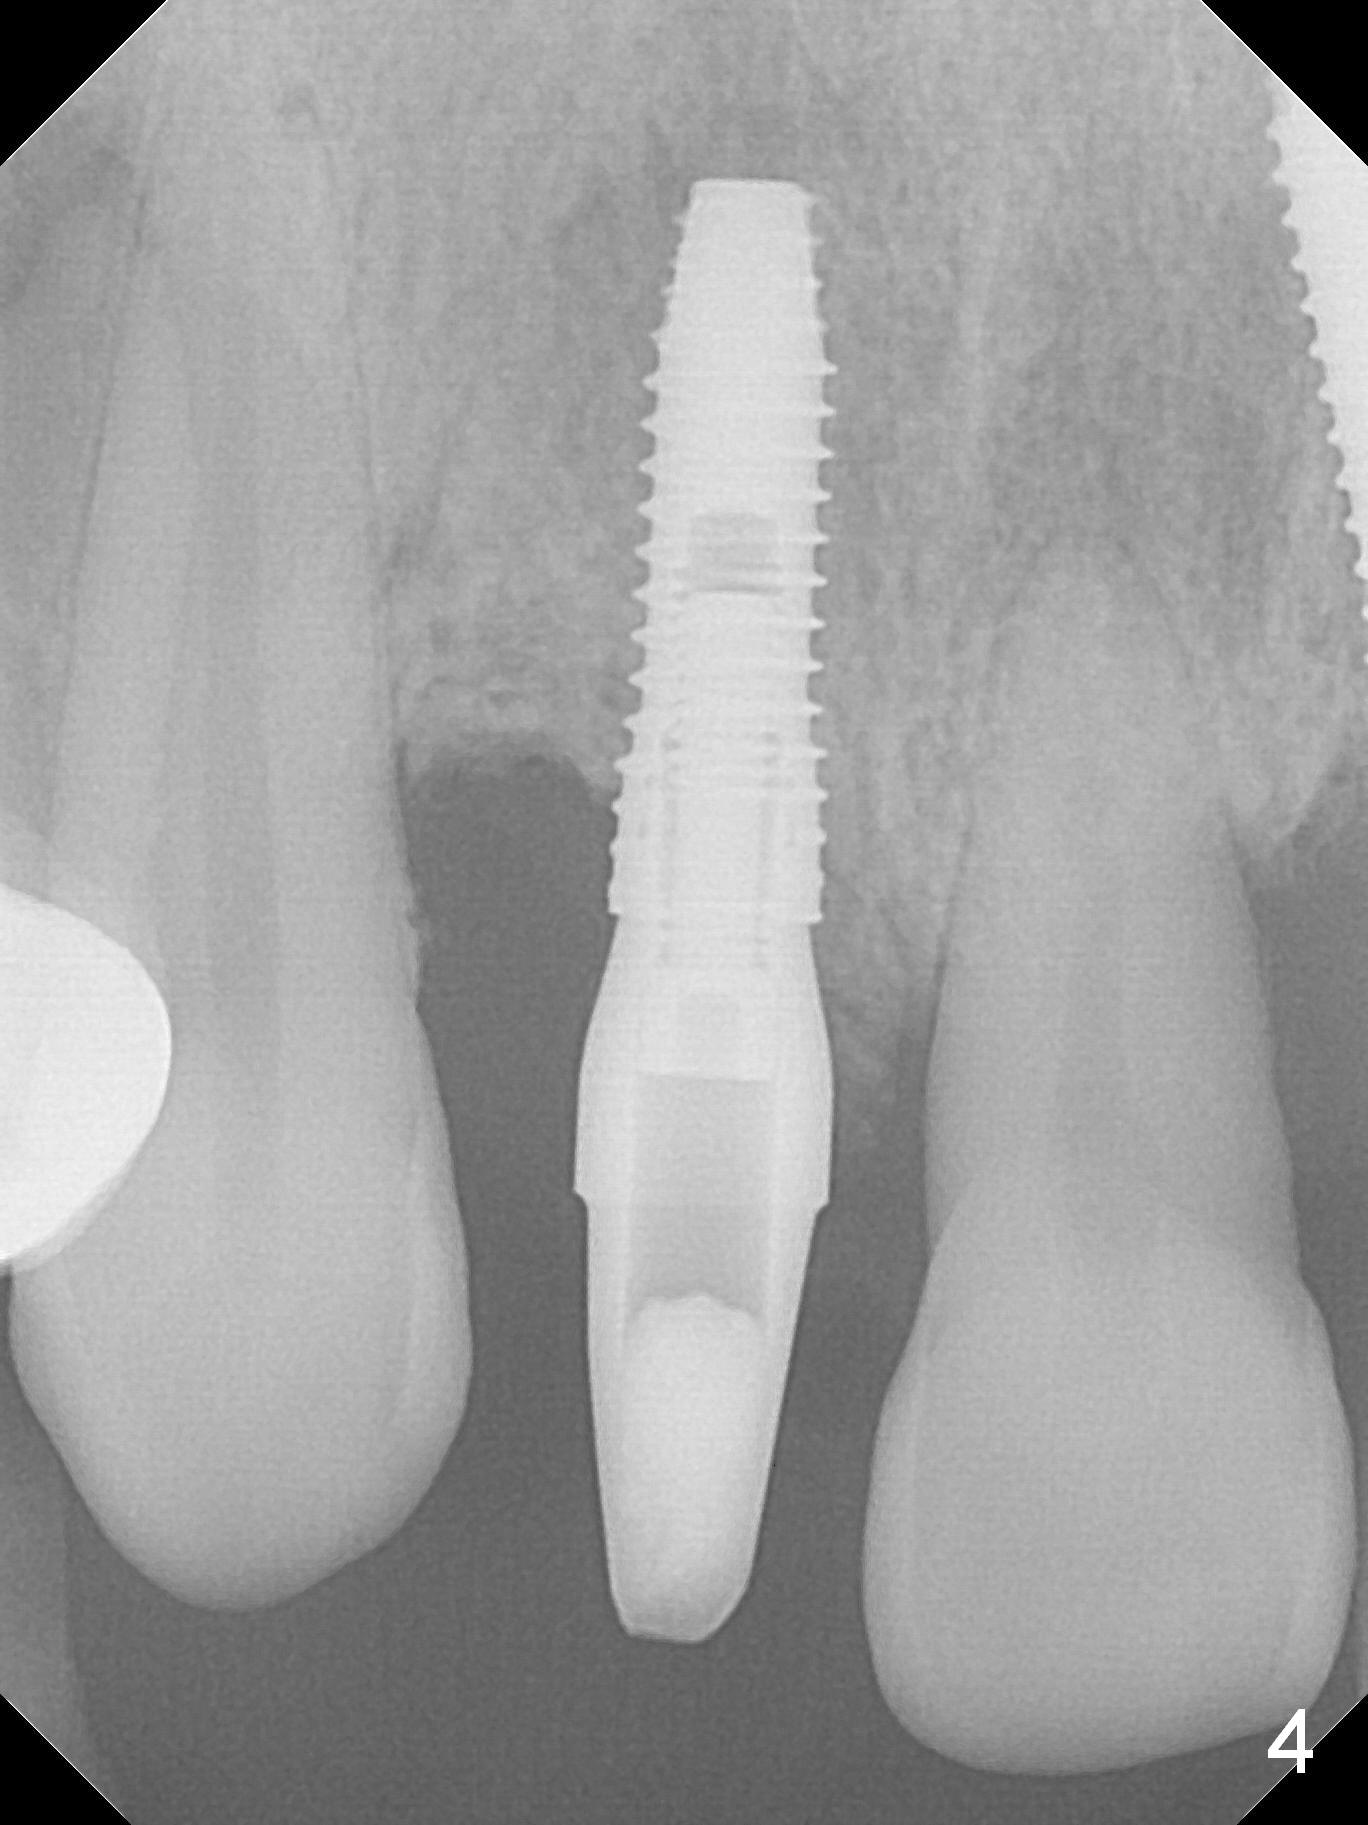

In fact the buccal plate feels to be perforated when 2 mm initial drill is being used probably at the deepest area of the concavity shown in Fig.2 (near B).  The trajectory is adjusted and the osteotomy is enlarged by 3 mm drill for 13 mm (Fig.3).  When a 3.8x13 mm implant is placed (50 Ncm), an angled abutment is used (Fig.4, 4.5x15°(A)5 mm).  As planned, a 3.8x13 mm implant is placed at #13, while bone graft is placed mesial and palatal to #15 implant.  No provisional is fabricated from #9 to 15 due to time limitation and lack of parallism between the abutments.